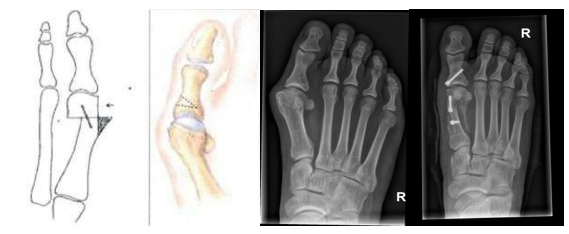

Ved operationen rettes storetåens mellemfodsknogle, som er gledet ud af position og danner knysten. Knoglen saves igennem, så ledhovedet (selve knysten) kan forskydes mod lilletåen. Det kan være nødvendigt at løsne stramme ledbånd omkring leddet for at opnå den ønskede korrektion.

Hos nogle patienter er den første knogle i storetåen (grundphalanx) også skæv. I disse tilfælde kan man fjerne en lille knoglekile, så tåen rettes yderligere op. Når knoglerne er bragt i korrekt stilling, fastgøres de med små skruer, som forsænkes i knoglen. Skruerne skal normalt ikke fjernes igen.